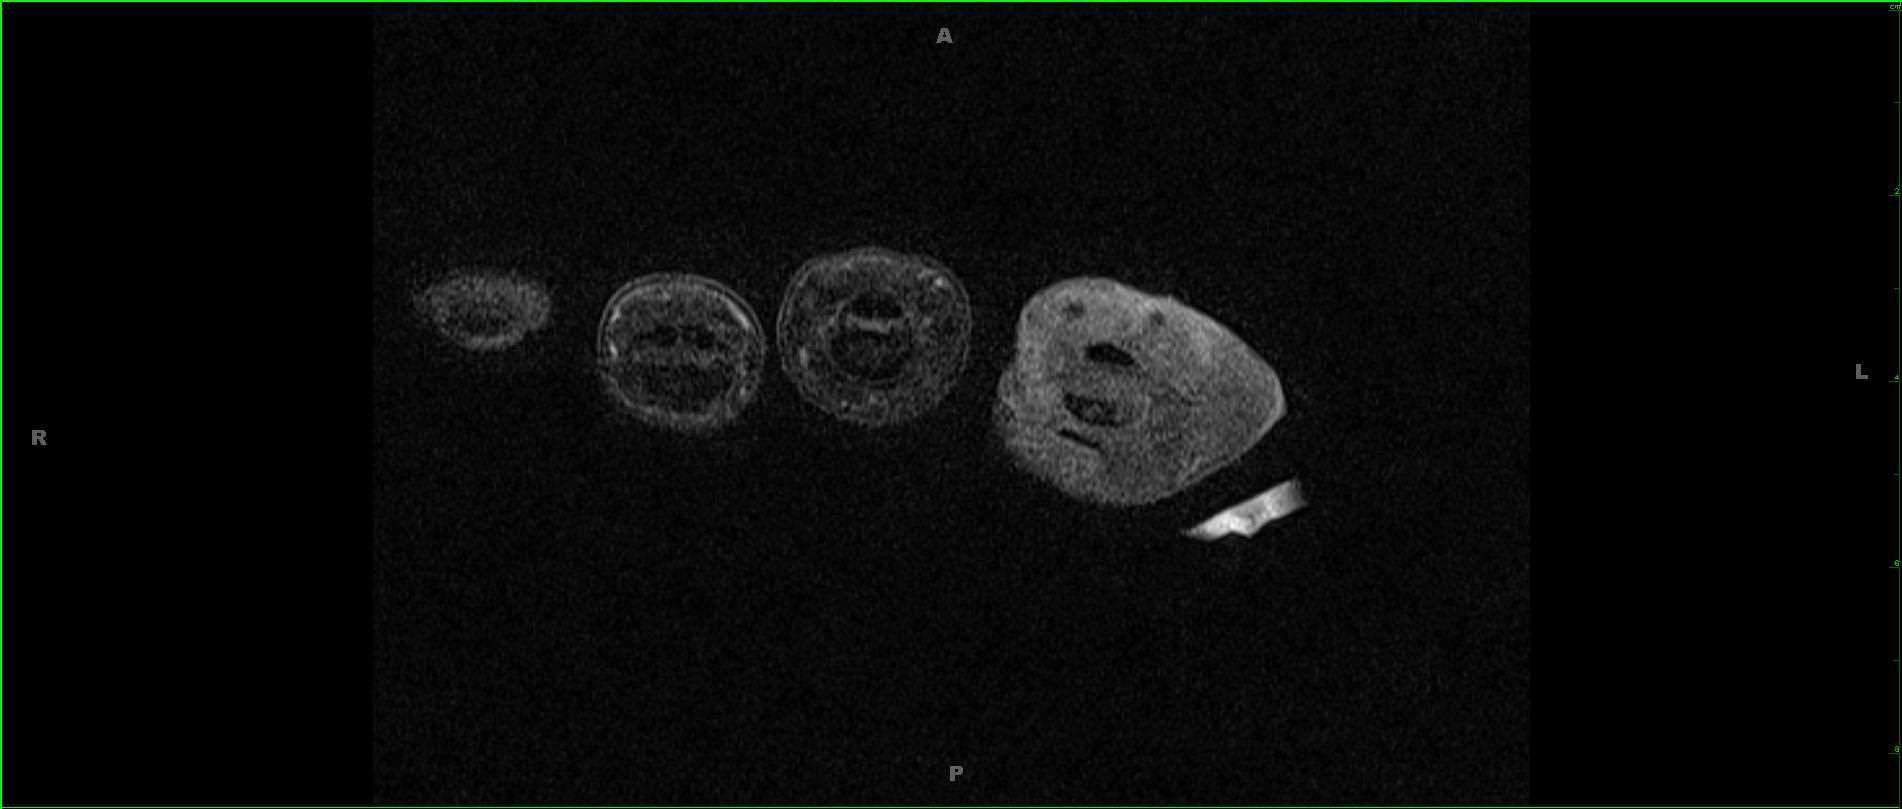

42-year-old male with gradually enlarging left thigh mass. Images demonstrate a multiseptated T1 hyperintense, STIR hypointense, heterogeneously enhancing mass enveloping the left femoral diaphysis and extending into the surrounding soft tissues. No periosteal reaction. There are enhancing, wispy, septations on the postcontrast images with more nodular excrescences at the inferior most aspect of the mass. On resection, this lesion was found to be a well-differentiated liposarcoma, which represents the second most common soft tissue sarcoma. Liposarcoma typically arise in adults between the ages of the 40 and 60 years. Typical locations include the extremities or retroperitoneum. Well-differentiated liposarcoma is the most common subtype, occurring in greater than 50% of cases. Extremity liposarcomas are typically slow growing and have variable rates of localized disease recurrence with deeper lesions more likely to recur. Primary surgical treatment is with wide local excision.